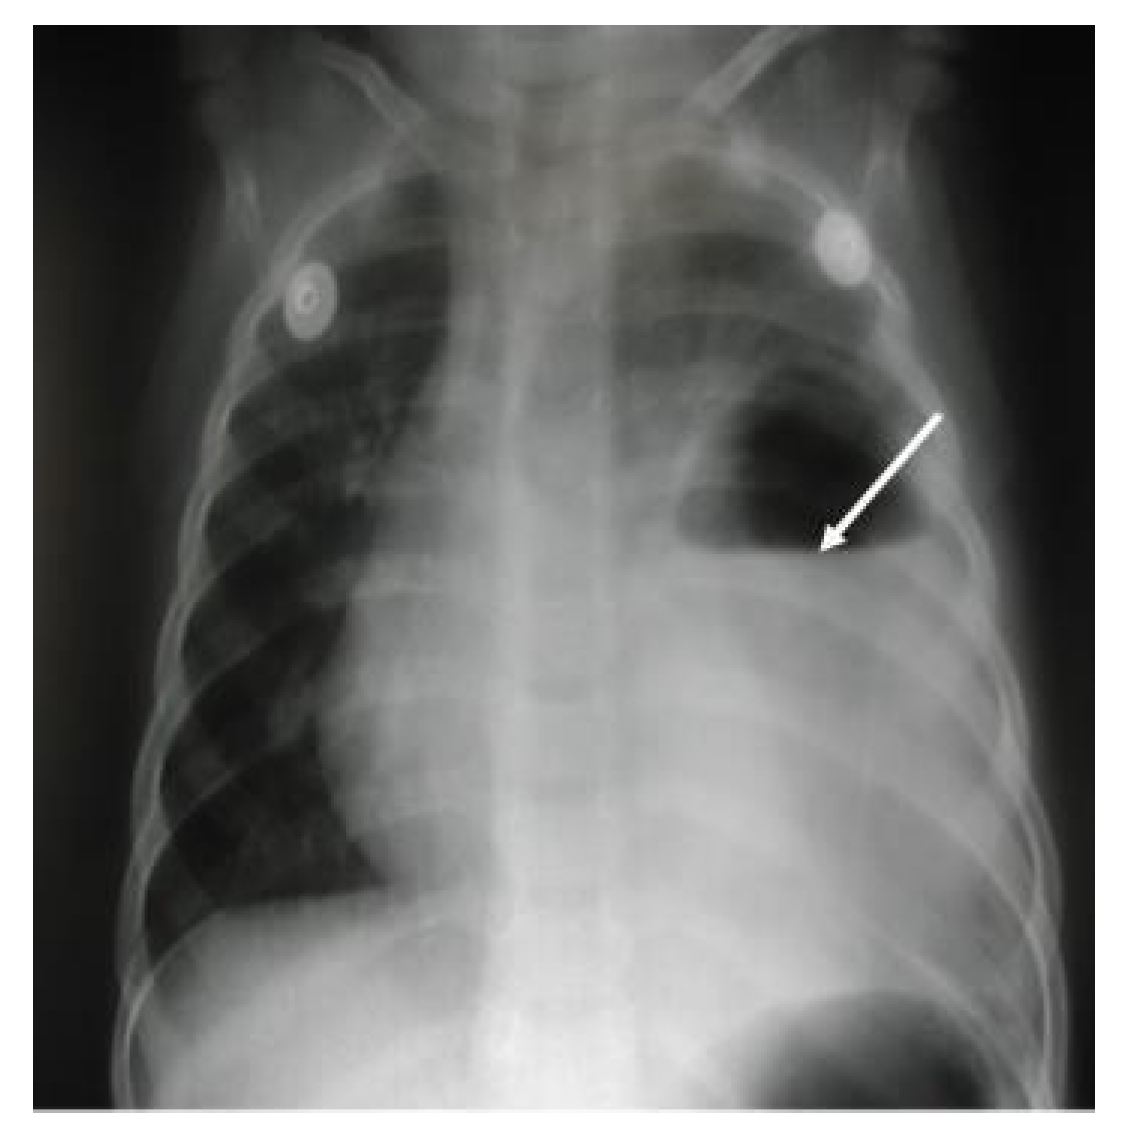

Figure 5. Large homogenous added density occupying most of the right side of the hemithorax with a large amount of air fluid in the superior aspect, as shown by the white arrow, silhouetting the cardiac border, costo- and cardiophrenic angles with no air bronchogram, suggesting large right-sided lung abscess with secondary mild hyperinflation on the left side of the lung.

A 21-month-old boy presented with an acute history of fever, cough, diarrhea, and poor appetite for a week. His medical history was unremarkable. On examination, he looked unwell, and his vital signs were as follows: temperature 38.9 °C, heart rate 160/m, respiratory rate 36/m, blood pressure 93/56 mmHg, and oxygen saturation 95% in room air. There was no finger clubbing. Chest examination revealed tachypnea and the use of accessory muscles (sub-costal and intercostal muscles) with markedly reduced breath sound on the right side, no bronchial breathing, a mild tenderness of the right hypochondrium, no lymphadenopathy, and the rest of the systemic exam was normal. Investigations had the following results: white blood 17.2 k/µL, predominantly neutrophils 12.4 k/µL, while lymphocytes 3.6 k/µL, Hb 9.8 g/dl, platelets 567 k/µL, C-reactive protein 157 mg/L, erythrocyte sedimentation rate 70 mm/h, normal electrolytes, negative blood culture, and negative mono spot test. Chest X-ray suggested a right-sided lung abscess (Figure 5), CT chest confirmed a large lung abscess and sequestration of the right lower lobe. The patient was treated with cefotaxime and vancomycin for 3 weeks. The patient was then scheduled for surgery (resection of the right lower lobe). He then completed 6 weeks of total therapy with no reported complications.